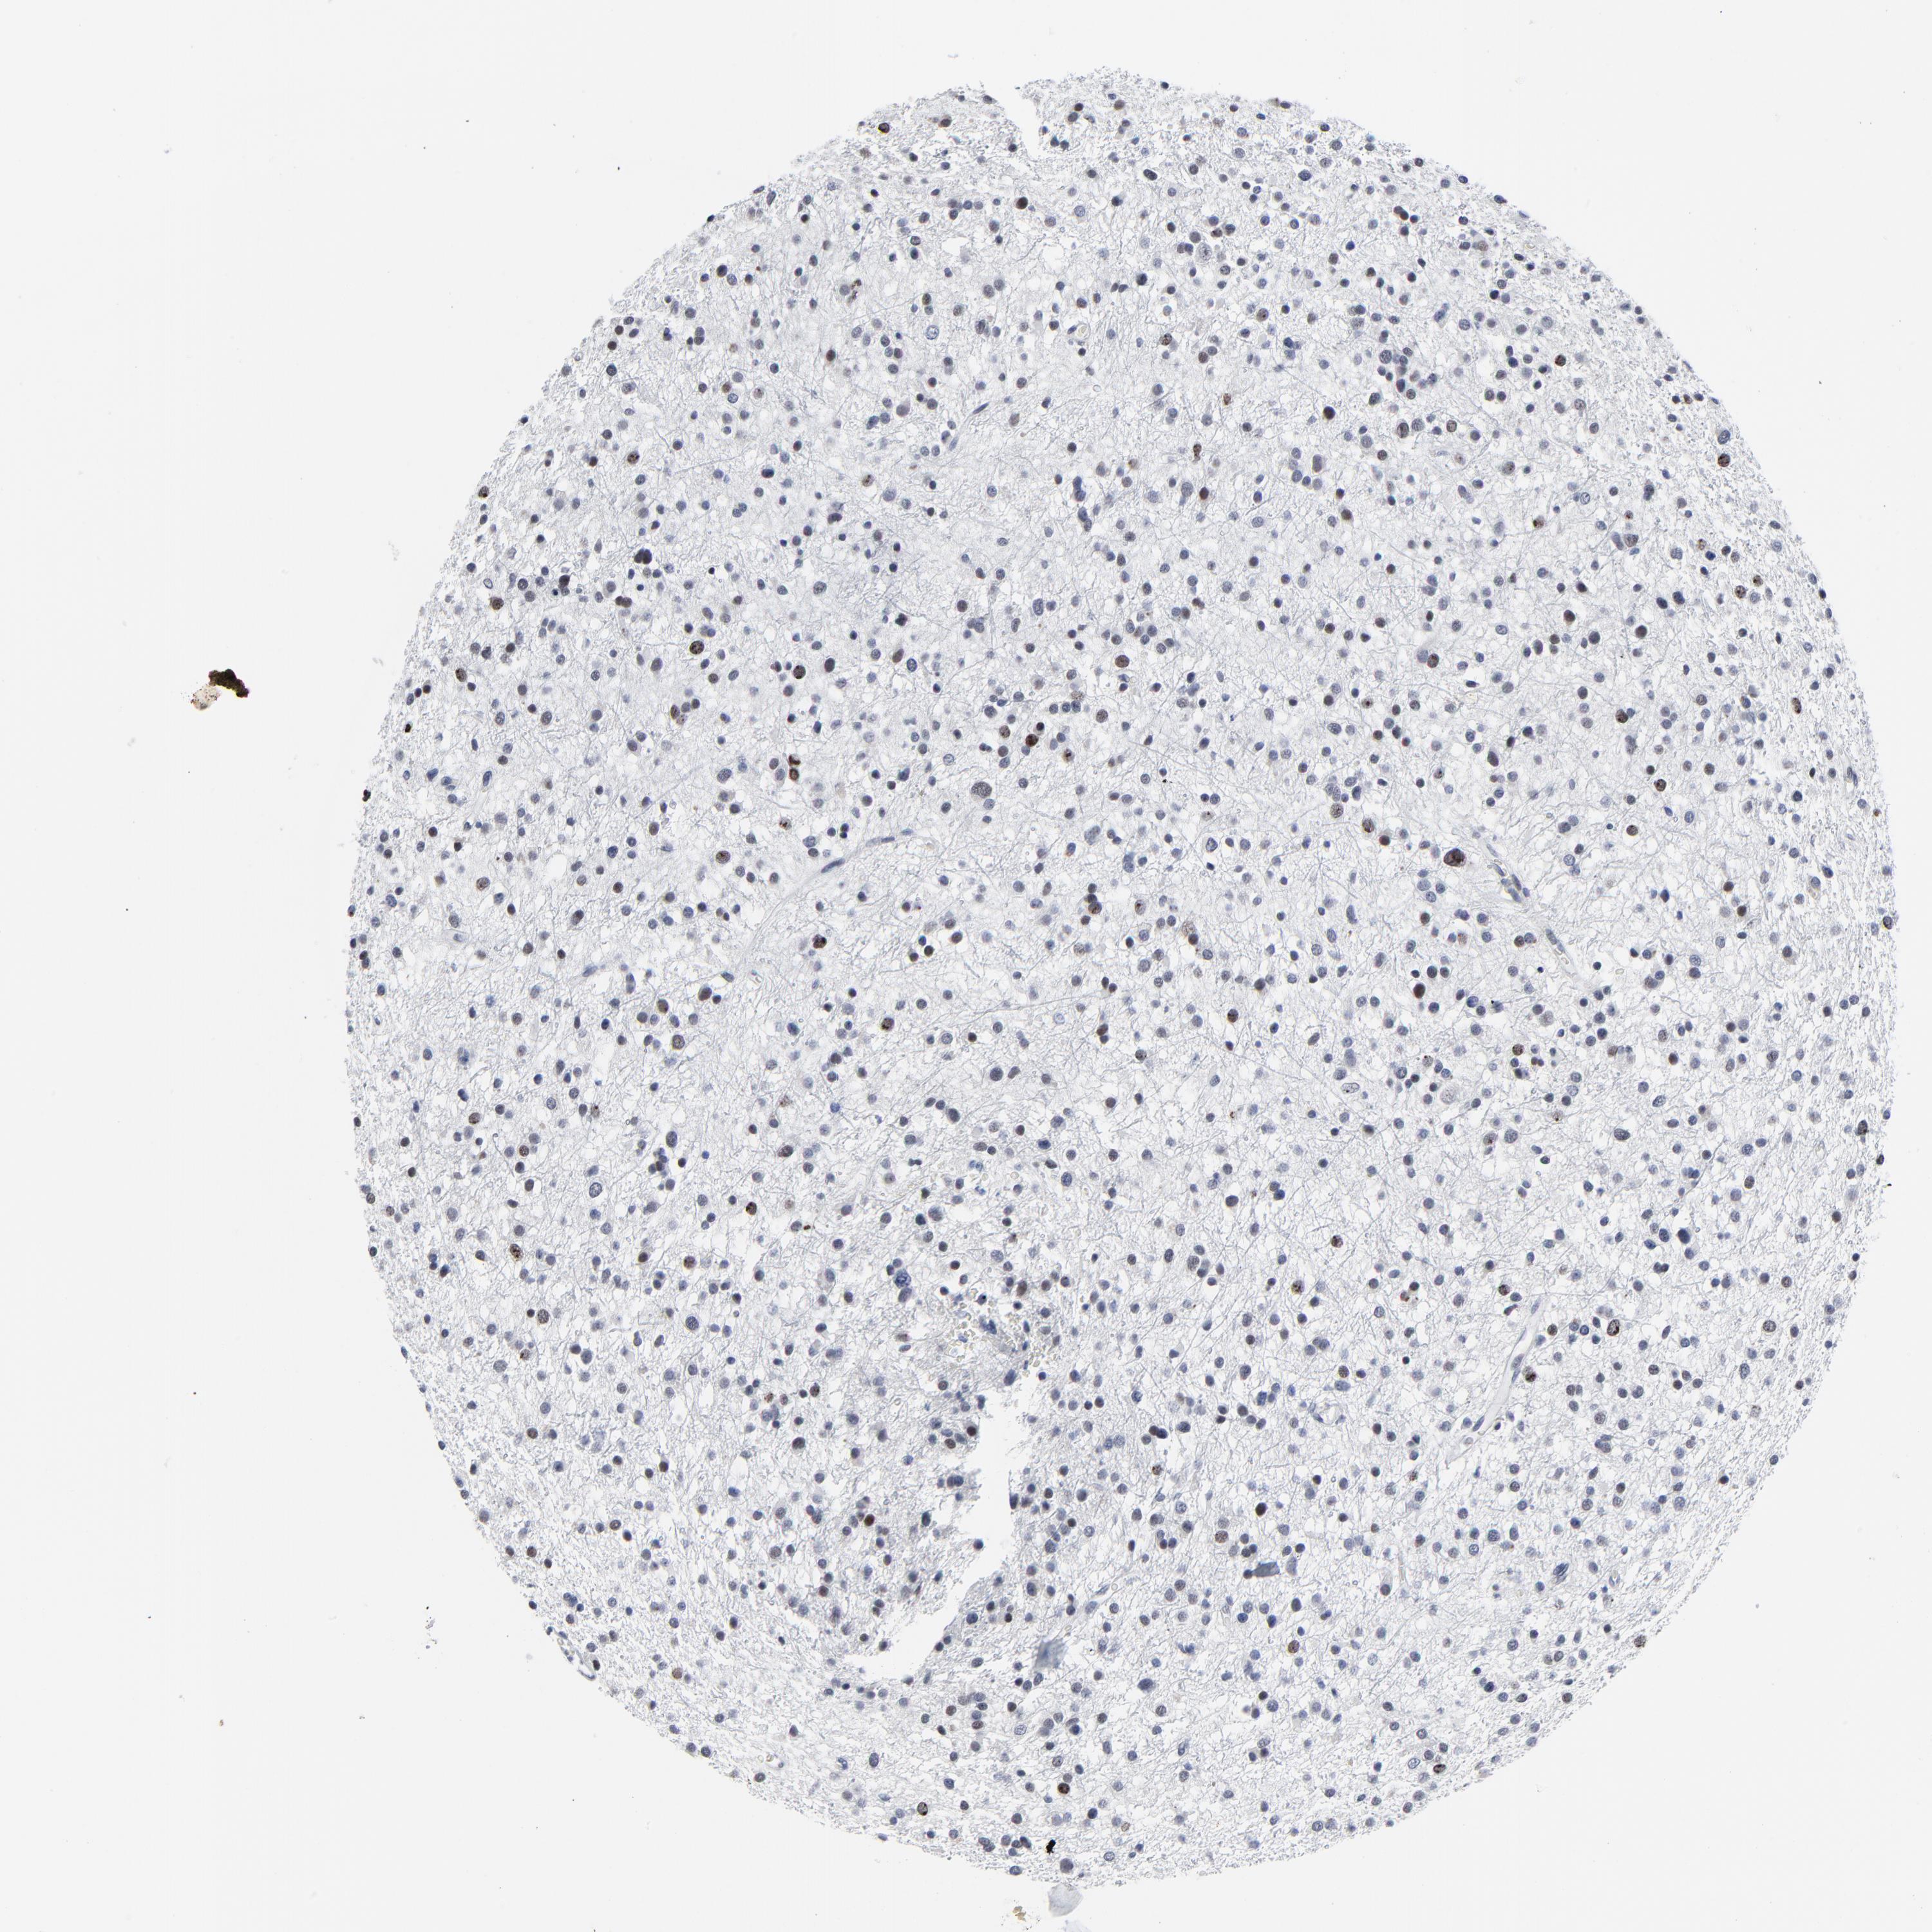

GLIOMA - Protein expressioni

A mouse-over function shows sample information and annotation data. Click on an image to view it in a full screen mode. Samples can be filtered based on level of antibody staining by selecting one or several of the following categories: high, medium, low and not detected. The assay and annotation is described here.

Note that samples used for immunohistochemistry by the Human Protein Atlas do not correspond to samples in the TCGA dataset.

Antibody stainingi

Antibody staining in the annotated cell types in the current human tissue is reported as not detected, low, medium, or high, based on conventional immunohistochemistry profiling in selected tissues. This score is based on the combination of the staining intensity and fraction of stained cells.

Each image is clickable and will lead to virtual microscopy that enables deeper exploration of all samples and also displays staining intensity scores, fraction scores and subcellular localization as well as patient and tissue information for each sample.

Antibody HPA003145

Staining

High

Medium

Low

Not detected

Intensity

Strong

Moderate

Weak

Negative

Quantity

>75%

75%-25%

<25%

None

Location

Nuclear

Cytoplasmic/membranous

Cytoplasmic/membranous,nuclear

Glioma, malignant, High grade

Glioma, malignant, Low grade